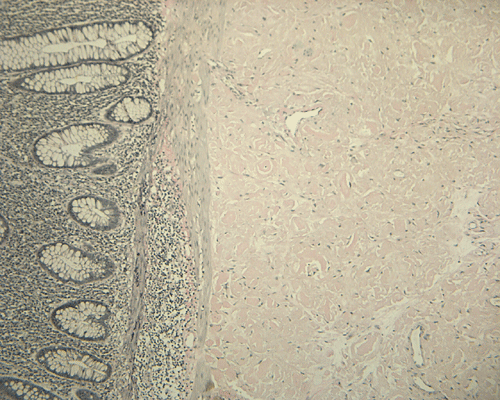

On low magnification, the mucosa appear intact and unremarkable. However, the submosa and muscular layer is replaced by a pale eosinophilic, hypocellular, amorphous material (Panel A). These material separate the smooth muscle bundles (Panel B and C). On Masson's trichrome, these material appears blue (Panel D). They are negative for elastic stain (Panel E). These material are stained orange by Congo Red stain (Panel  F and G) which gives an apple green birefrigence on polarized light (Panel H). Electron microscopy was performed and revealed non-branhing straight fibrils ranging from 6.6 to 8.3 nm in diameter consistent with amyloid.

Amyloid can be detected on routine hematoxylin and eosin (H&E) slides, all forms of amyloid deposits are amorphous and homogenous, with pale eosinophilic areas 15. Microscopic characterization of amyloid by special studies is necessary to confirm diagnosis of amyloidosis. Congo red histochemical stain remains gold standard for diagnosis and characterize by common to all amyloid aggregates orange or red color on light microscopy and clear apple-green birefringence under polarised light 1, 2. Most of the other stains available are not recommended to be used alone and are listed with decreasing specificity and sensitivity: Sirius red, thioflavine T, thioflavine S, toluidine blue, p-dimethylaminobenzaldehyde-nitrite, alcian blue, and crystal violet 15. Electron microscopy studies indicate that the basic assembled unit is a thin filament of about 4 nm in diameter, and that the mature fibrils consist of a few such proto-filaments aligned in parallel, often with a twist 2. Some other authors describe amyloid filaments under electron microscope as loose meshwork of 7–10 nm wide rigid, non-branching, hollow fibrils of indeterminate length. The fibrils measure from 30 to more than 1000 nm in length and are usually found in aggregates in extracellular spaces 15, 16.